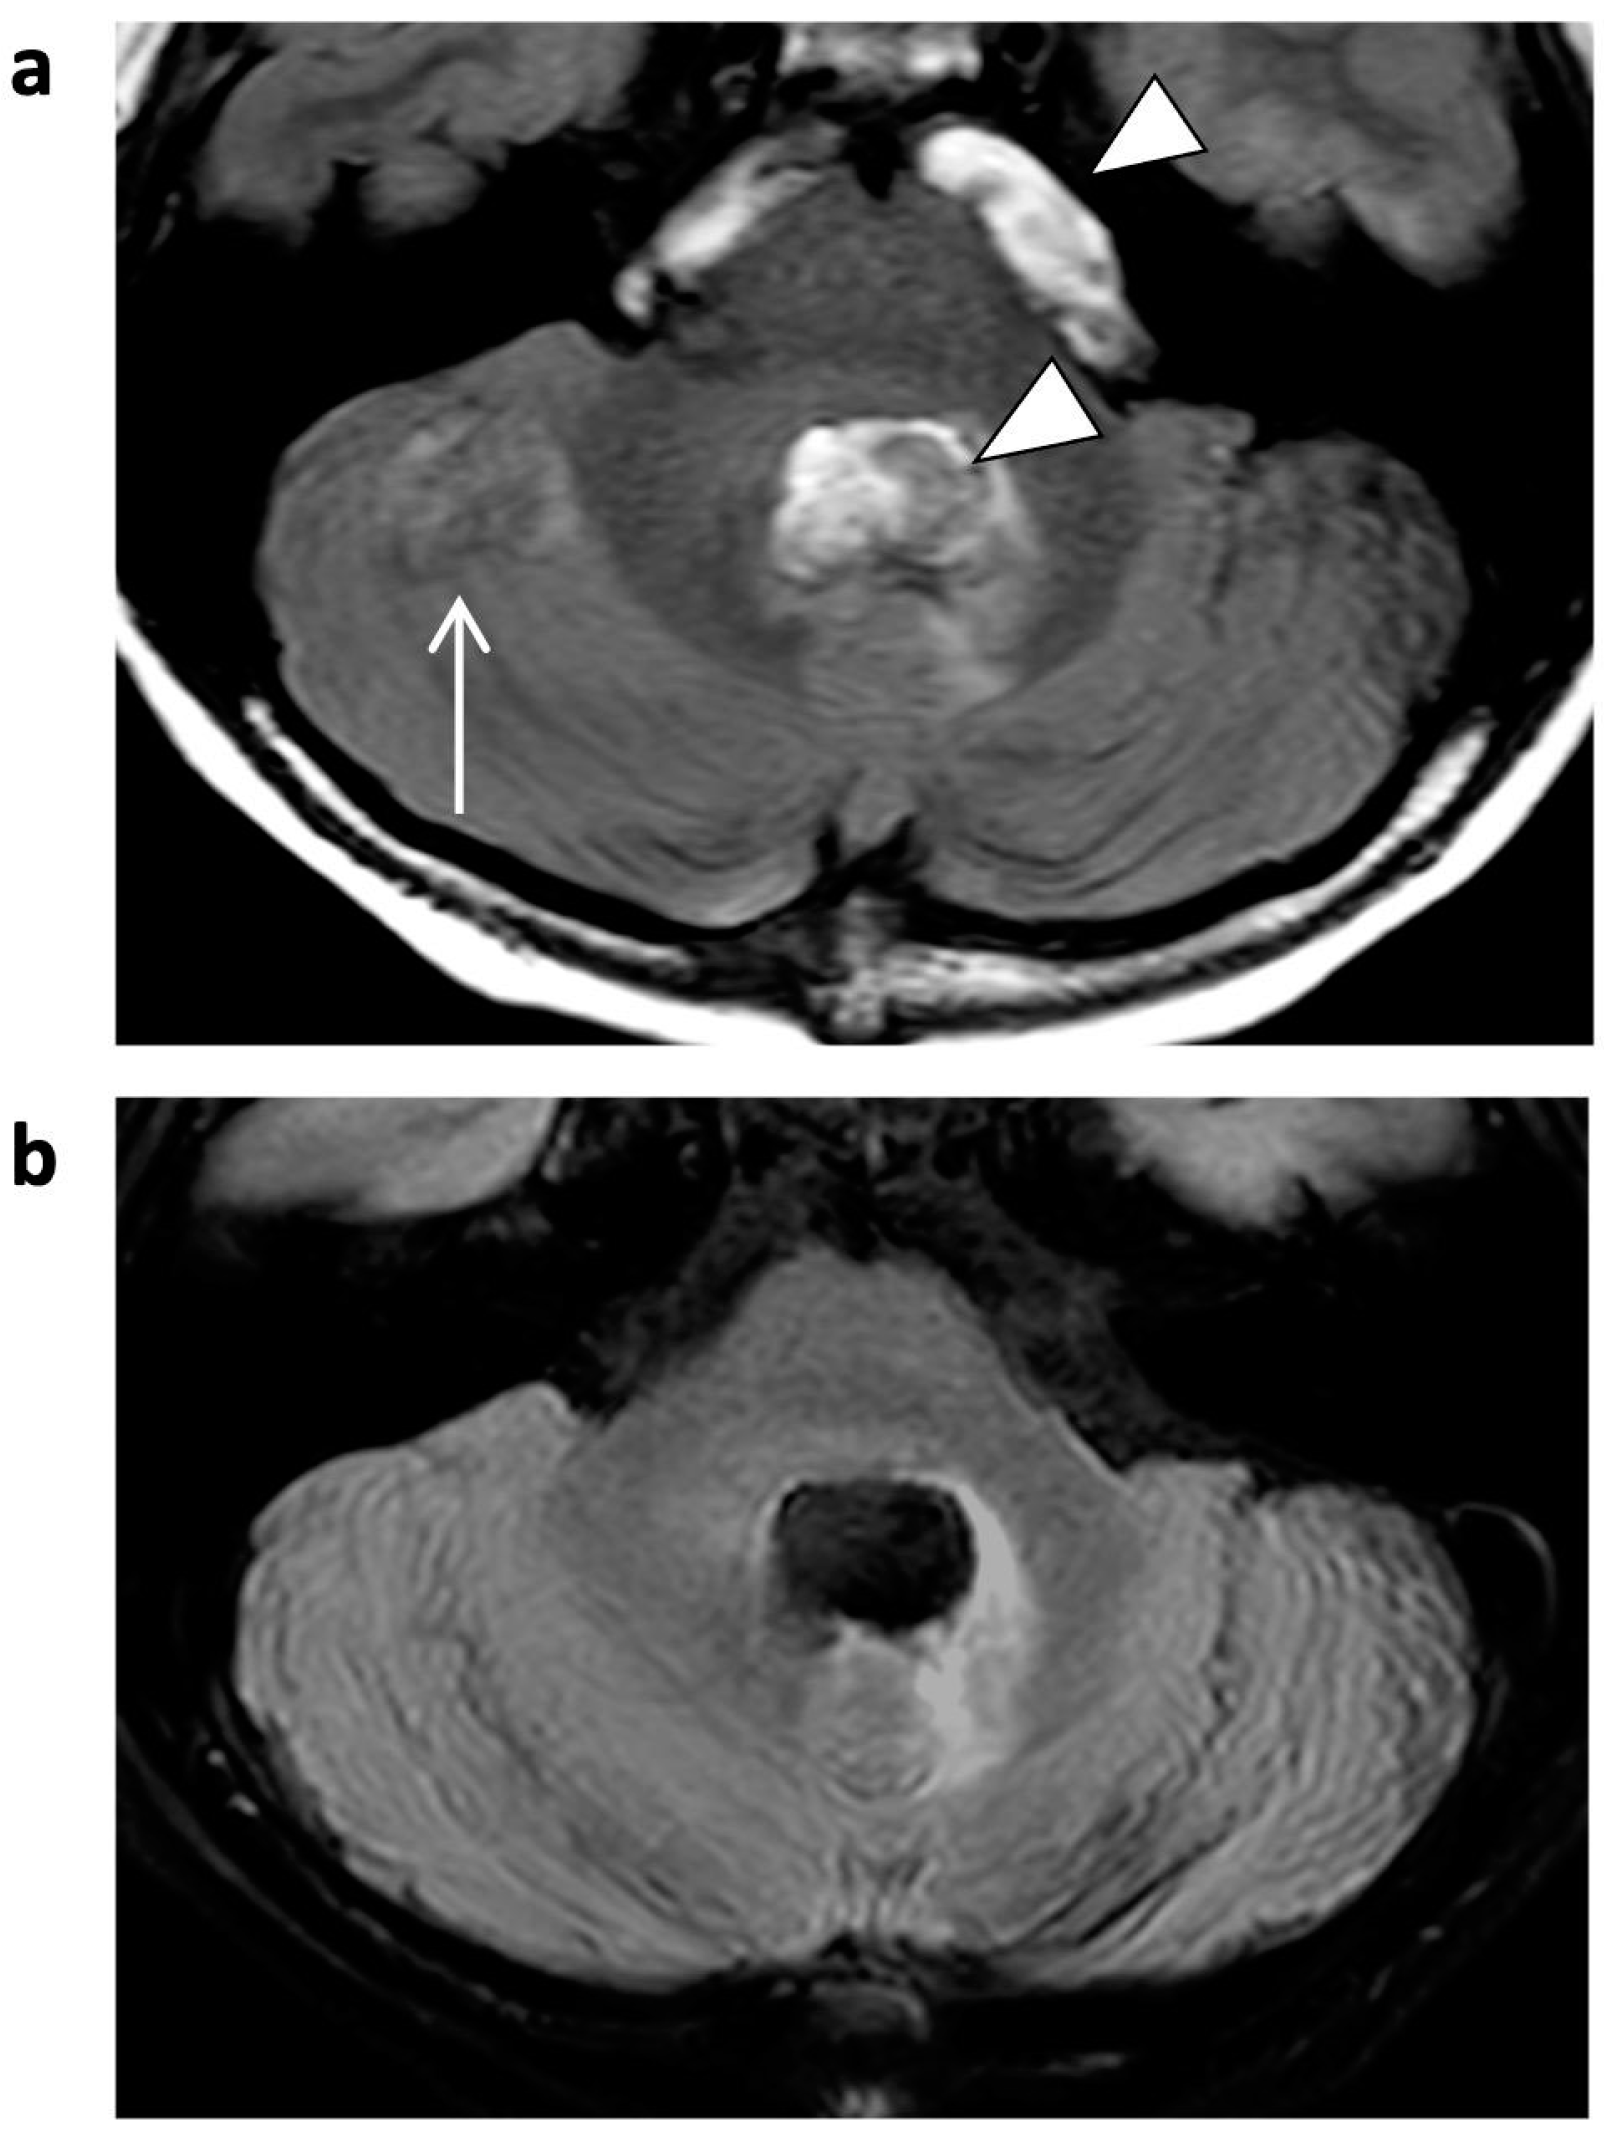

Figure 6.

FLAIR images of a 5-year-old male patient with astrocytoma (post-resection). Bright CSF-flow-related enhancement (FRE, arrowheads) in fourth ventricle and prepontine cisterns is seen in SENSE FLAIR (a), not present in CS FLAIR (b). As a consequence, the CSF-dependent ghosting artifacts (arrow) did not occur.